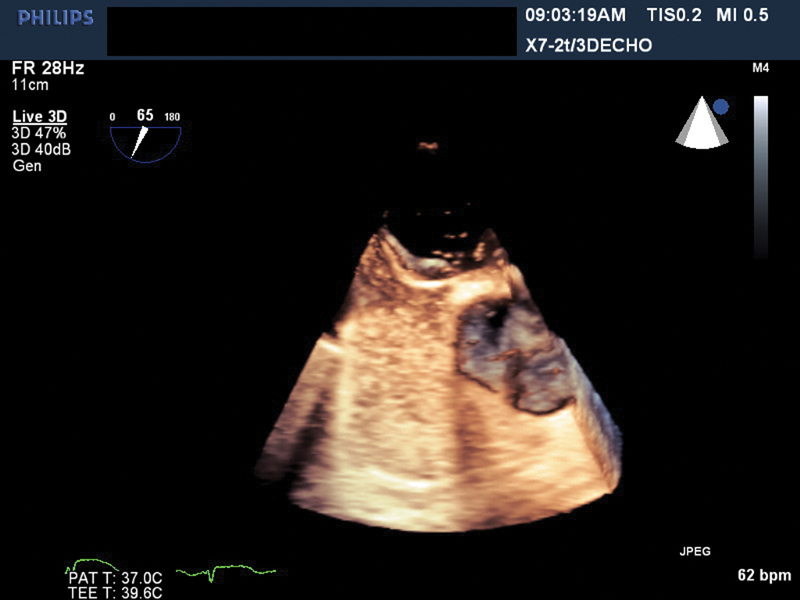

فحوصات تشخيصية لبعض امراض القلب والشرايين التاجية